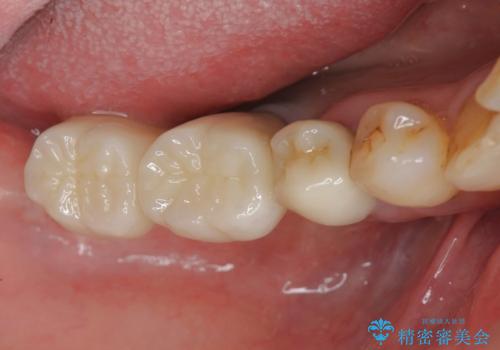

- 81.4万円 (straumann社製インプラント×2 アバットメント×2 仮歯×2 骨造成 ジルコニアクラウン×2)費用は治療当時の料金となります

入れ歯に替わりインプラント治療を行ったことでしっかりと物が噛め、食事ができるようになり大変喜んでいただくことができました。